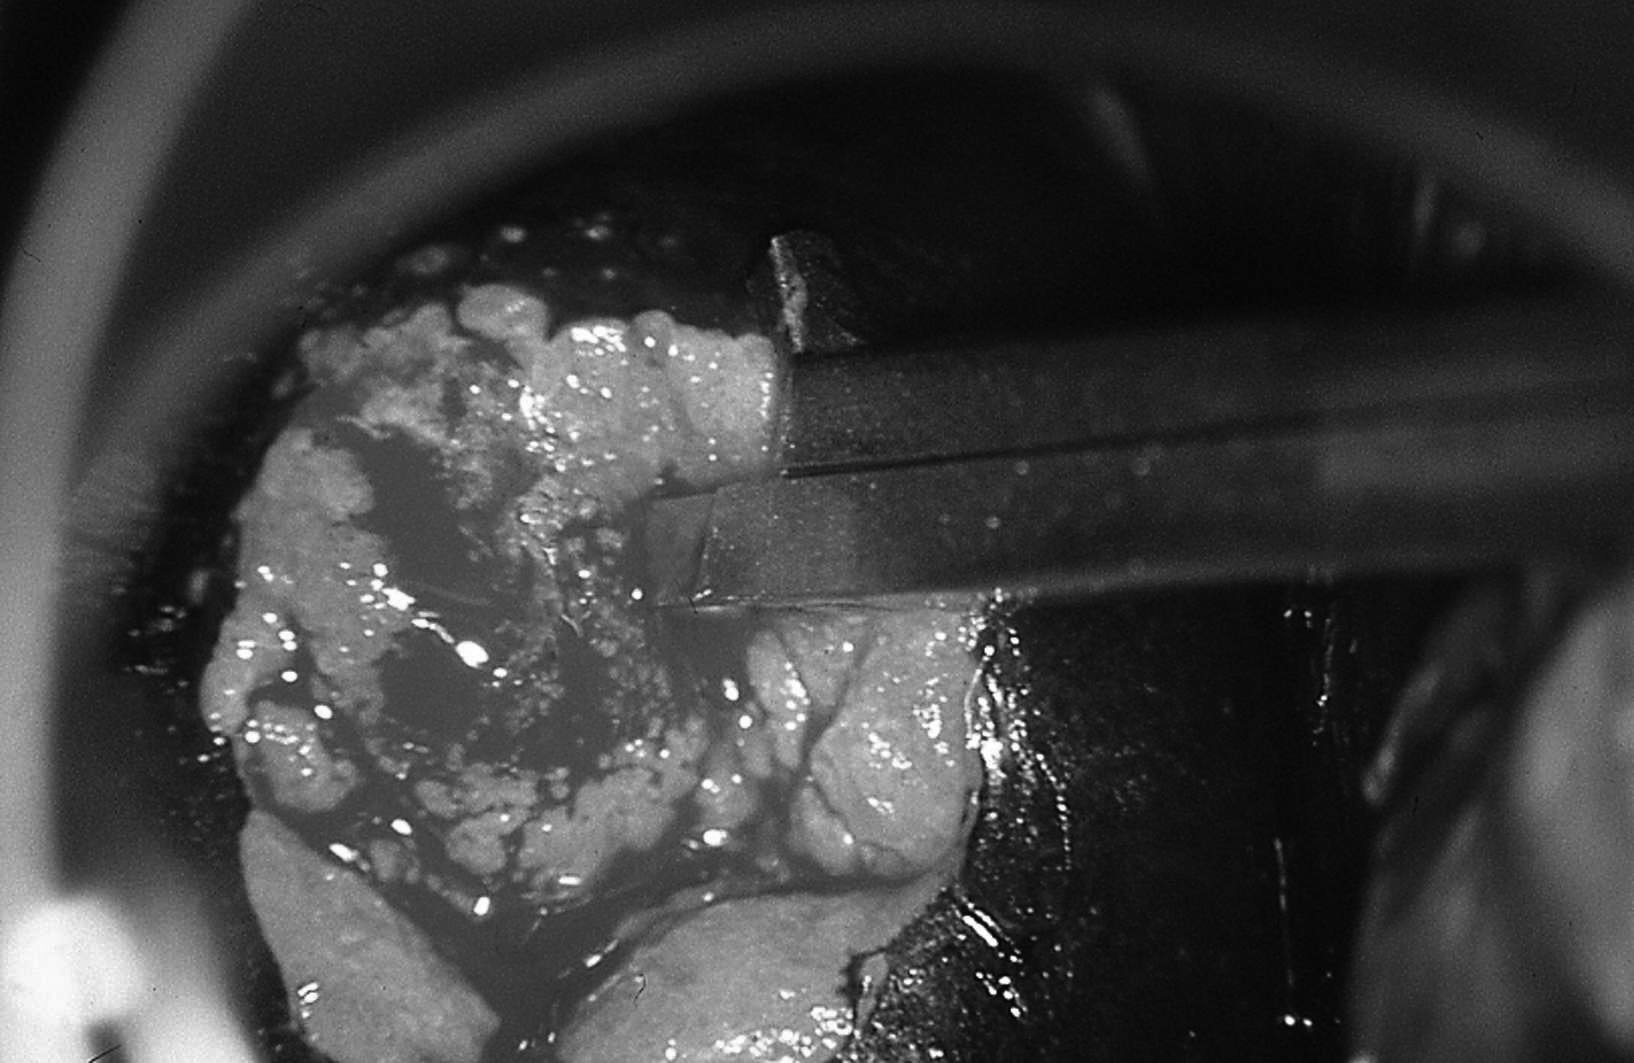

Figure 18.10 Biopsie cervicale au niveau de la jonction squamo-cylindrique

Figure 18.10 Biopsie cervicale au niveau de la jonction squamo-cylindrique.

À la fin de l’examen, la ou les biopsies sont pratiquées sous contrôle colposcopique sur les zones les plus suspectes. Ce geste est indolore (figure 18.10).